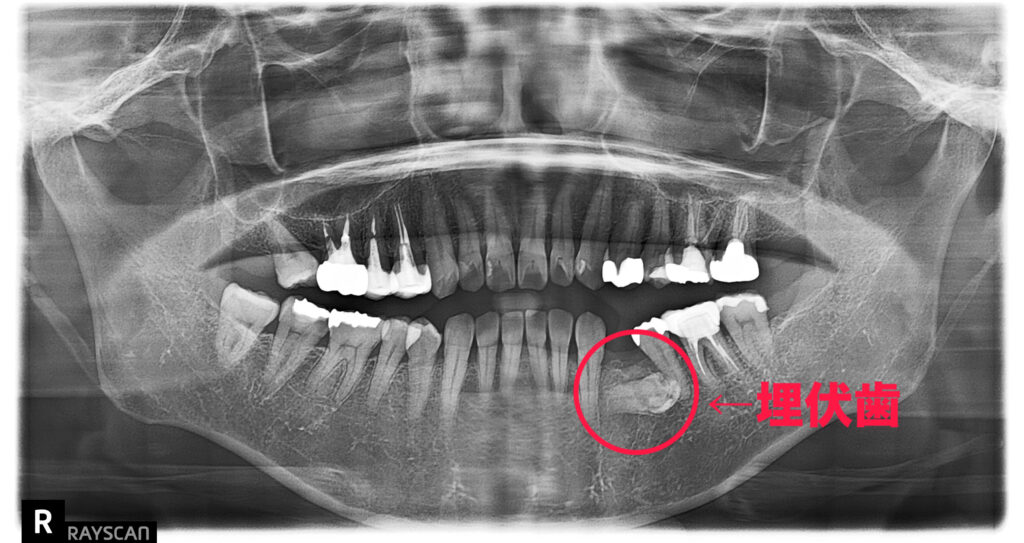

【先天的な原因(生まれつきの要因)】③ 埋伏歯(まいふくし)

歯が顎の骨の中に埋まったまま出てこない状態を埋伏歯といいます。本来萌出して歯列を支えるはずの歯が機能しないため、空隙が生じることがあります。